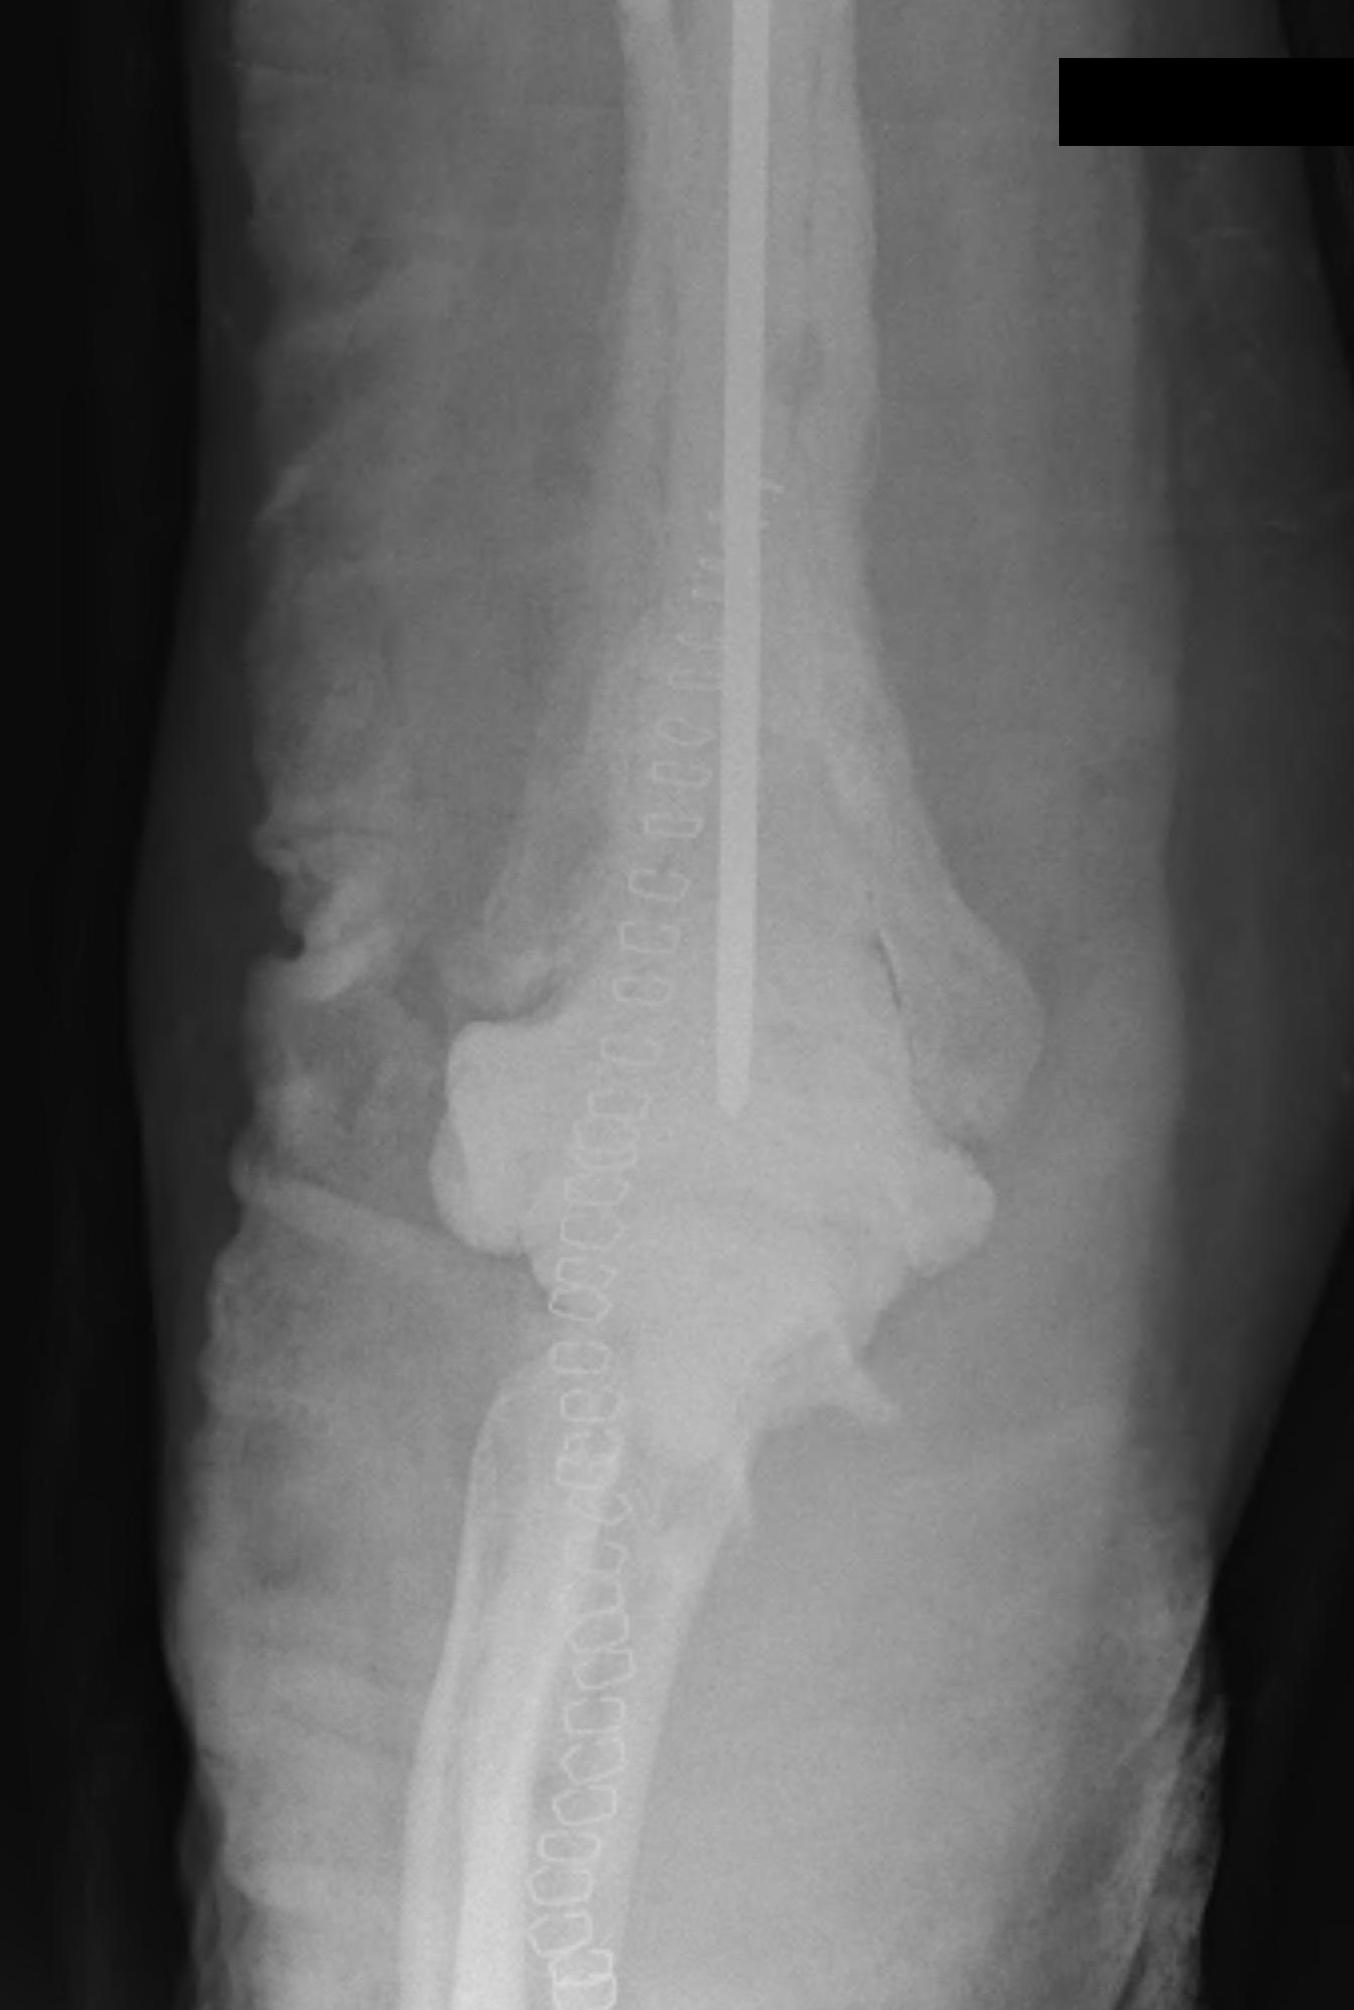

Periprosthetic Fracture